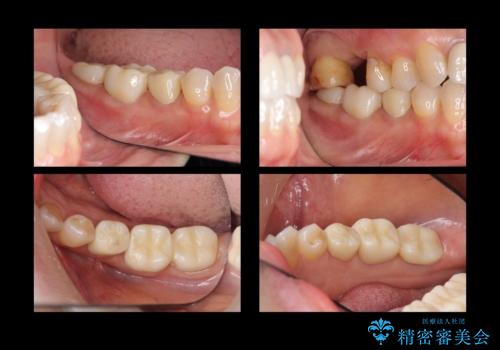

- 右下奥歯(7番)の高さがなく、かぶせ物(クラウン)にするためにあらかじめ歯周外科手術を行いました。(クラウンレングスニング)

- 56.1万円(右下567 ジルコニアクラウン11万円×3 歯周外科手術APF 15万円 仮歯1万円×3)費用は治療当時の料金となります

歯の高さを出すとかぶせ物(クラウン)がはずれにくくなります。

今回は右下7番が神経のない歯だったため、クラウンにして割れにくくしています。